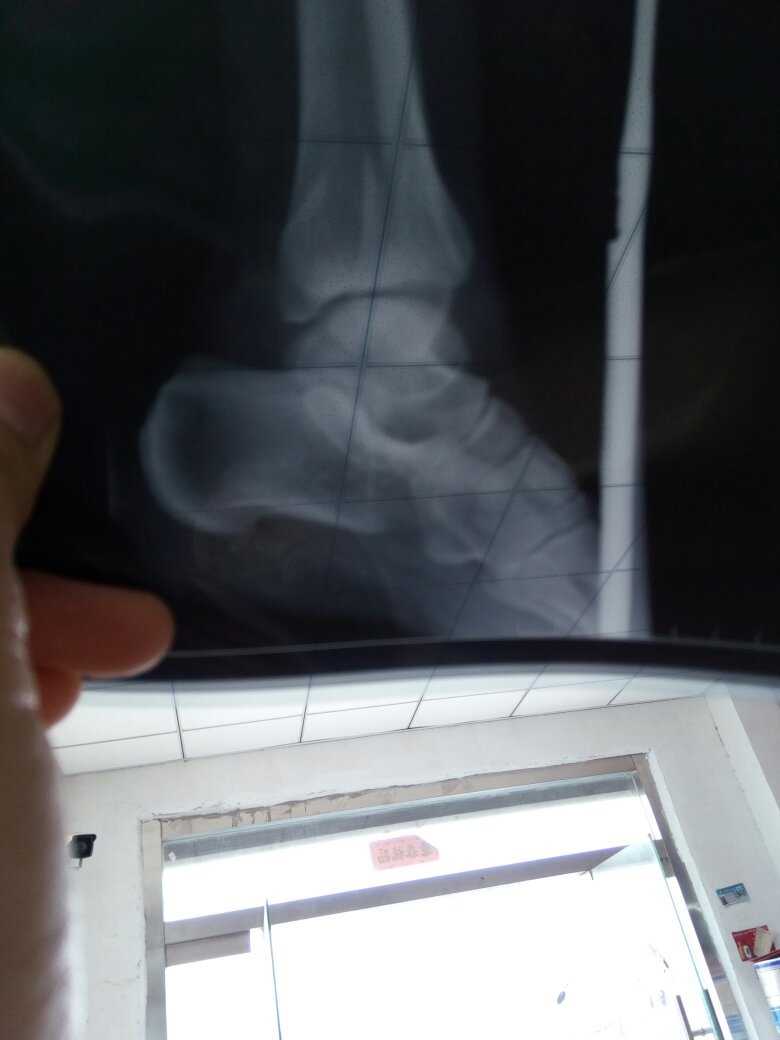

怀孕七个月了,左脚踝两边骨折石膏固定的,谁能帮我看看片子骨折严重吗 点击展开 133*****340_heC3 2016-09-22 13:41 满意回答 从片子上看,踝关节骨折确实比较严重,有错位。如果你没绣否糕有怀孕的话,笼貌肯定是需要朗脑立马做手术的。 匿名用户 2016-09-22 13:53 宝宝知道提示您:回答为网友贡献,仅供参考。 相关问题 脚踝处轻微骨折如果用石膏固定要固定多久 骨折后要拆石膏了,只是轻度骨折,可是脚踝? 骨折后要拆石膏了,只是轻度骨折,可是脚踝?